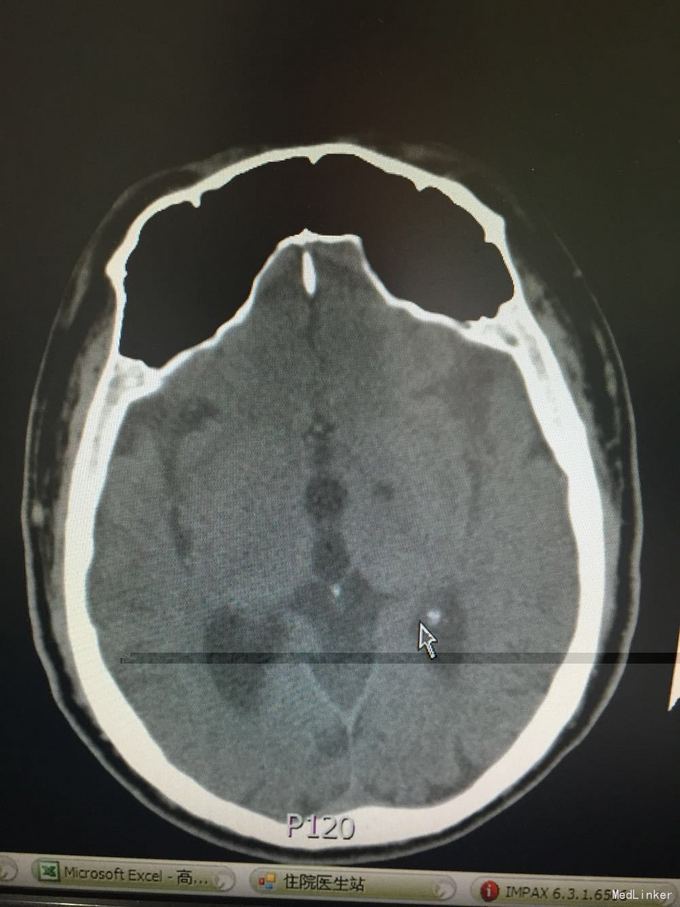

1脑梗死 2肺炎 3高血压3级 4.2型糖尿病 患者行动脉溶栓术,手术顺利,术后安返病房,查体:血压170/89 轻度嗜睡状态,言语笨拙,查体合作,双侧瞳孔等大同圆,对光反射存在,双眼轻度左侧凝视受限,鼻唇沟对称,伸舌居中,右上肢肌力4级,右下肢制动,左侧肢体肌力5级,右侧肌张力减低。病理征阳性,处置:动态监护,右下肢制动24小时,改善循环、神经保护、改善脑灌注、抗炎、化痰补液 对症支持治疗。

三天后,患者病情稳定,无饮水呛咳,无发热。查体:血压:173/105mmHg,神志清醒,言语略笨拙,双侧瞳孔等大同圆,对光反射存在,双眼轻度左侧凝视受限,鼻唇沟对称,伸舌居中,右上肢肌力5-级,左侧肢体肌力5级。右侧肌张力减弱,右下肢病理征(+),双肺闻及湿罗音。